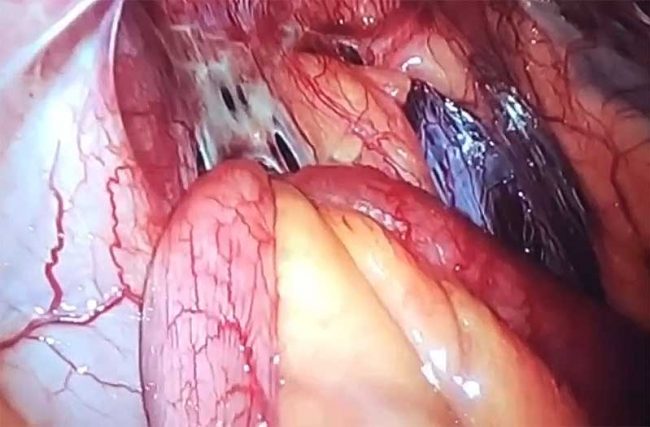

New technique for repairing Diastasis Recti

New technique for repairing Diastasis Recti by Dr. Iraniha Diastasis Recti or diastasis of Rectus muscles is a common condition when the anterior abdominal wall muscles called rectus muscles have separated from each other and weakened the core muscle strength. This condition also associated with abdominal wall bulge with abnormal body posture, lower back pain…